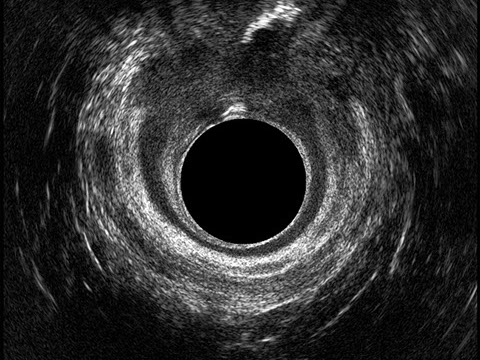

L’ecografia transanale è un esame diagnostico per immagini che consiste nell’introduzione di un trasduttore ad ultrasuoni. Le immagini qualitativamente migliori del canale anale sono ottenute usando un trasduttore rotante, montato in un manipolo rigido, che fornisce un’immagine a 360°. Con le apparecchiature più moderne è anche possibile ottenere immagini tridimensionali.

L’ecografia transanale permette di distinguere la sottomucosa che riveste il canale anale, lo sfintere anale interno, e lo sfintere anale esterno.